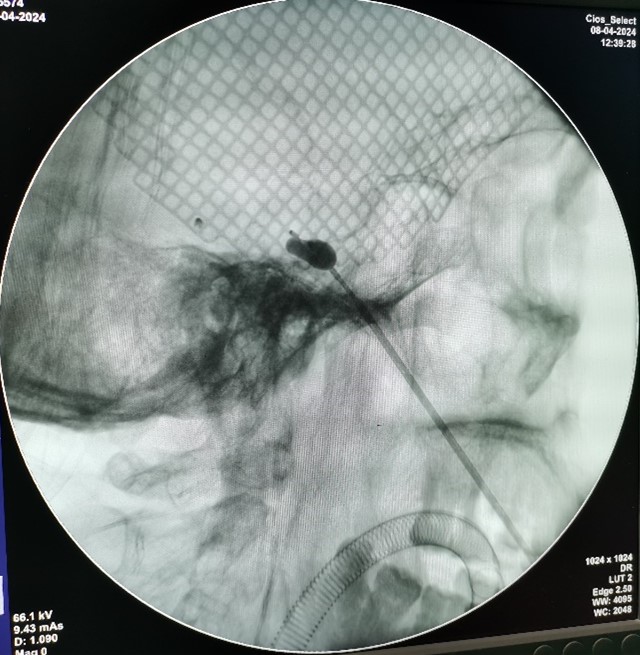

4月8日,洋县人民医院在我院神经外科周乐主任医师、麻醉科蒋文军主治医师的指导下,完成了洋县县域内首例经皮穿刺球囊压迫术治疗三叉神经痛手术,解除了患者的病痛,填补了洋县县域内医疗技术在该项目的空白。

经皮穿刺三叉神经球囊压迫术是重要的三叉神经痛外科微创介入治疗技术。该技术在X线引导下,用特制的穿刺针,将球囊导管置入麦氏囊,压迫三叉神经半月神经节,阻滞三叉神经痛觉传导通路,进而达到治疗三叉神经痛的目的。手术在全麻下进行,治疗过程中患者全程无痛苦。手术创伤小,术后患者恢复快。